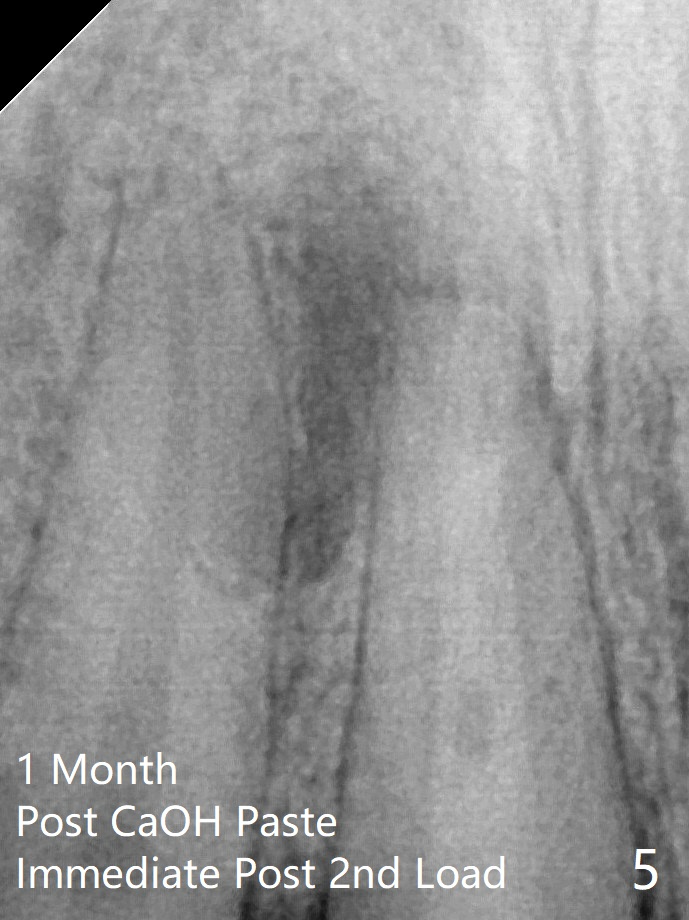

P: 氢氧化钙糊剂。术后一个月,右上1根尖没有触痛,而左上1仍有,置换糊剂后拍摄根尖片显示右上1根尖阴影仍旧很大(图五),什么时候完成永久性根管充填?